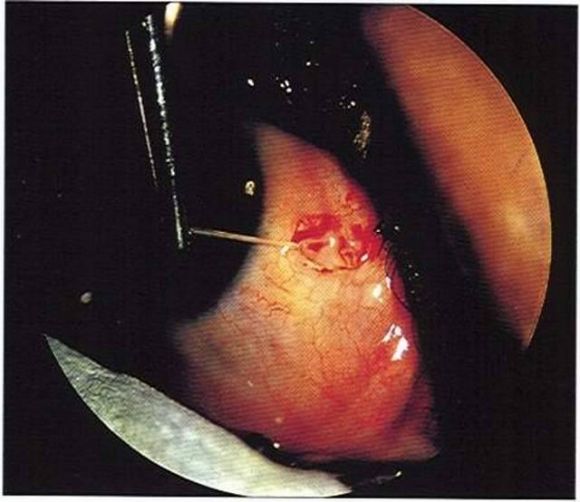

≪MOVIE≫ Worm in the eye removed in Calicut, Kerala